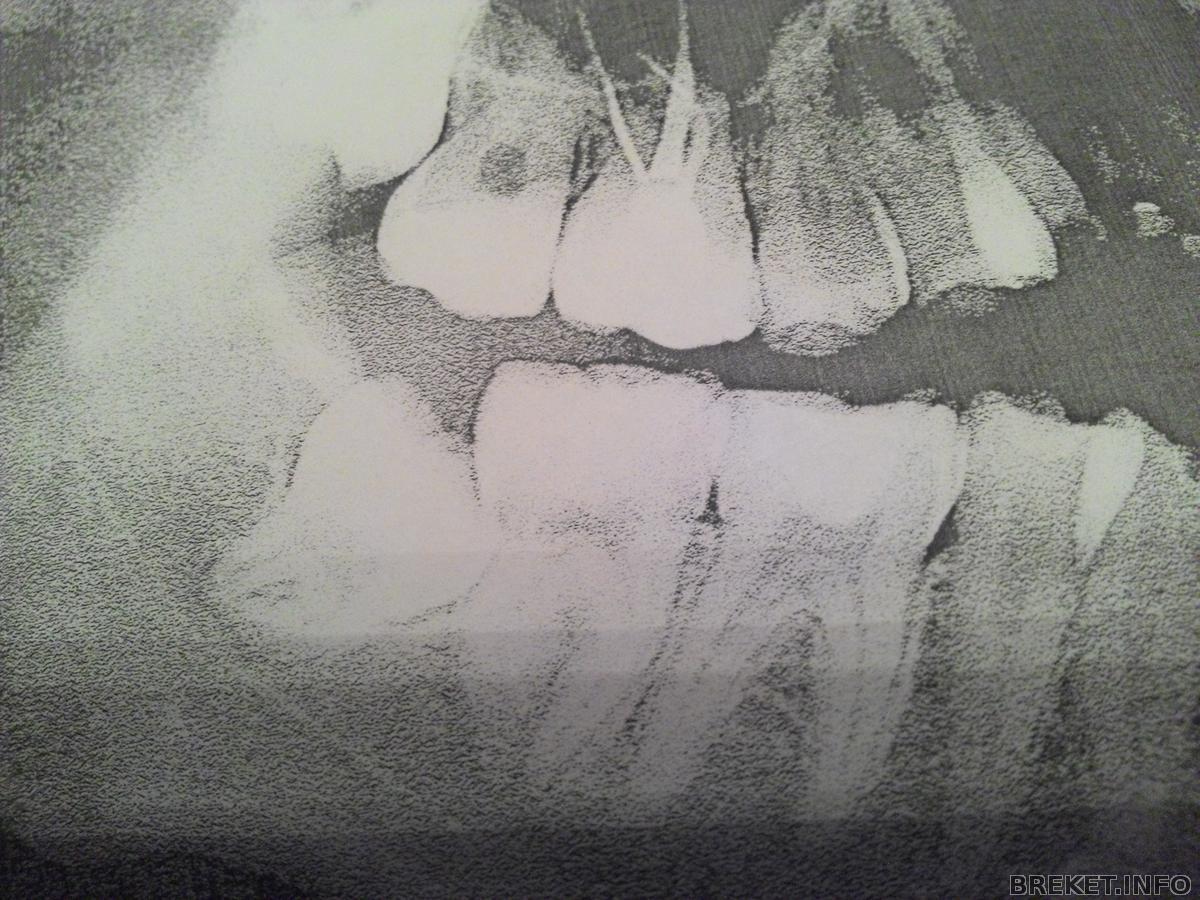

Для установки брекетов на НЧ осталось удалить ретинированную восьмерку, только она в "интересном положении" находится, под 45 градусов. Скажите, у кого-нибудь была подобная ситуация? Тяжело такую 8 удалять? Долго удаляли? Отек или синяк оставался?

Что-то страшно мне удалять ее...

Приближается срок ставить брекеты на ВЧ. Скорей всего на следующей неделе осмелюсь и пойду удалять нижнюю ретинированную восьмерку. Надеюсь, что не сильно щека отекет... так как сессия... но нужно делать сейчас, так как на ВЧ брекеты установлены еще в ноябре. Вот думаю, ставит на НЧ Damon Clear, только больно уж новые цены кусаются. У кого-нибудь стоять керамические даймоны на обеих челюстях? Как ощущения? Не отваливаются от нагрузок?